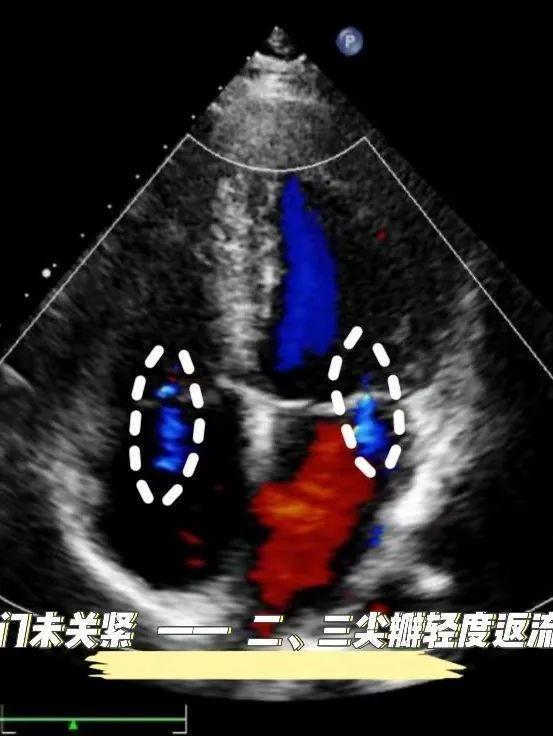

例如,心脏彩超主要检查房子(心房/室)是否增大,墙壁(房/室壁)是否增厚,墙壁是否出现孔洞(房/室缺),门窗(房室瓣、半月瓣)是否关闭良好,以及房子的稳固情况(心功能)等。

二、三尖瓣轻度返流